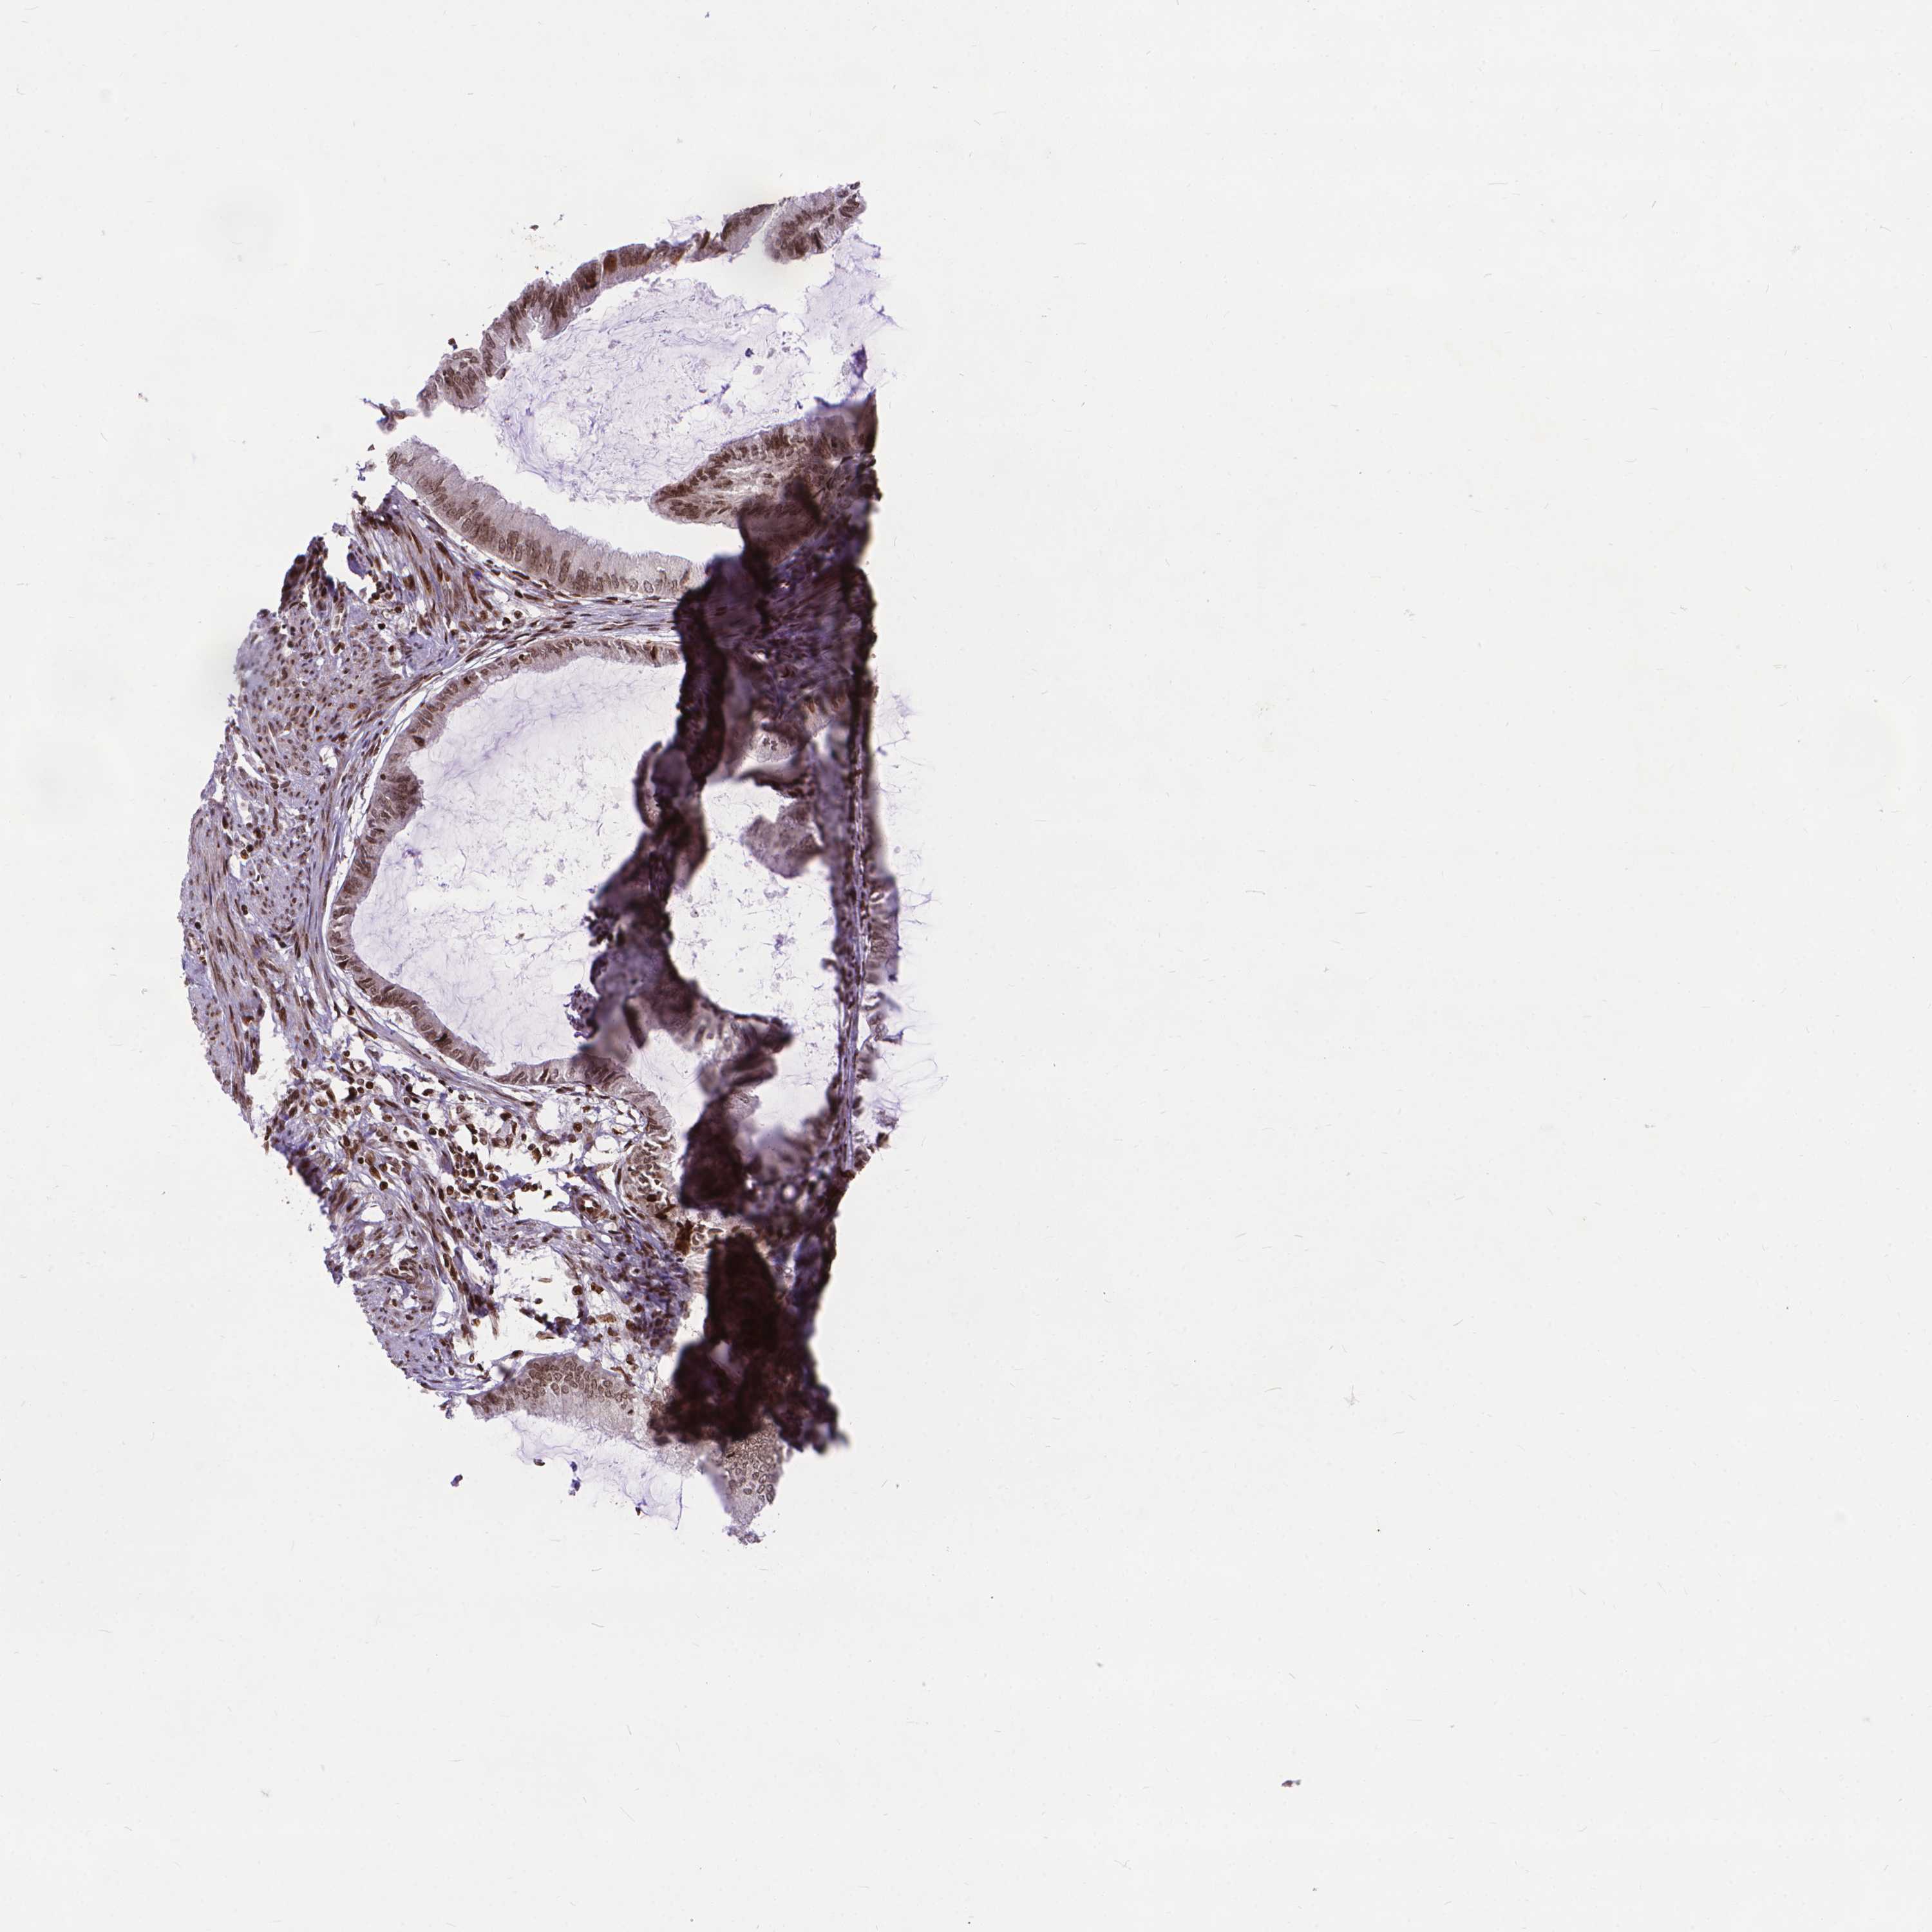

ENDOMETRIAL CANCER - Protein expressioni

A mouse-over function shows sample information and annotation data. Click on an image to view it in a full screen mode. Samples can be filtered based on level of antibody staining by selecting one or several of the following categories: high, medium, low and not detected. The assay and annotation is described here.

Note that samples used for immunohistochemistry by the Human Protein Atlas do not correspond to samples in the TCGA dataset.

Antibody stainingi

Antibody staining in the annotated cell types in the current human tissue is reported as not detected, low, medium, or high, based on conventional immunohistochemistry profiling in selected tissues. This score is based on the combination of the staining intensity and fraction of stained cells.

Each image is clickable and will lead to virtual microscopy that enables deeper exploration of all samples and also displays staining intensity scores, fraction scores and subcellular localization as well as patient and tissue information for each sample.

Antibody HPA065214

Staining

High

Medium

Low

Not detected

Intensity

Strong

Moderate

Weak

Negative

Quantity

>75%

75%-25%

<25%

None

Location

Nuclear

Cytoplasmic/membranous

Cytoplasmic/membranous,nuclear

Adenocarcinoma, NOS

Adenocarcinoma, metastatic, NOS